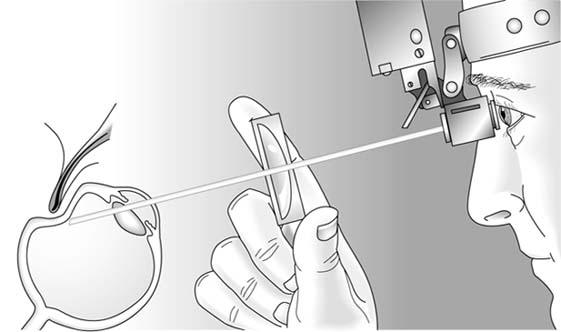

Figure 2-16

Figure 2-16: Examination with head-mounted binocular indirect ophthalmoscope. A 20-diopter hand-held condensing lens is used. (Photo by M Narahara.)

Scleral depression (Figure 2-18) is performed as the peripheral retina is being examined with the indirect ophthalmoscope. A smooth, thin metal probe is used to gently indent the globe externally through the lids at a point just behind the corneoscleral junction (limbus). As this is done, the ora serrata and peripheral retina are pushed internally into the examiner's line of view. By depressing around the entire circumference, the peripheral retina can be viewed in its entirety.

Figure 2-18

Figure 2-18: Diagrammatic representation of indirect ophthalmoscopy with scleral depression to examine the far peripheral retina. Indentation of the sclera through the lids brings the peripheral edge of the retina into visual alignment with the dilated pupil, the hand-held condensing lens, and the head-mounted ophthalmoscope.